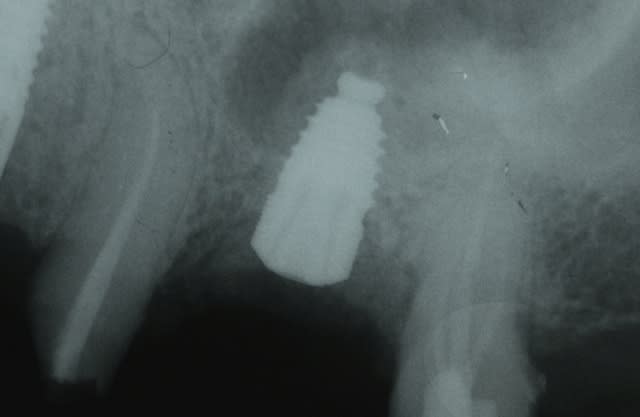

Présentation du cas : extraction de 26 , attente 2 mois cicatrisation, hauteur résiduelle estimé à 5 mm , mauvaise surprise après avoir oté le provisoire, très belle crète bien large mais invaginée en son centre.

Forage au milieu à 3mm + effraction du plancher ,manoeuvre de Walsava OK, bourrage au Gen Oss (0.5cc) , re Walsava, et implant IDCAM 10/5.2 bloqué au maximum .

sur la radio post-op, l'espace entre l'implant et la pré-molaire, non comblé, ne causera pas de problème ?

J'aurais tenter un SA-3, pour comblé plus large et évité ce vide, qui est un ramasse bactérie dans le sinus...

peut être , mais je parie plutot sur une remontée générale du plancher dans ce secteur, vu la faible distance avec la prémolaire.

On va faire comme d'hab, on va attendre les photos à 6 mois pour savoir qui a raison.

Tiens jette un coup d'oeil sur la partie mésial de cet implant sans comblement où 3 spires ont été englouties dans la cicatrisation osseuse